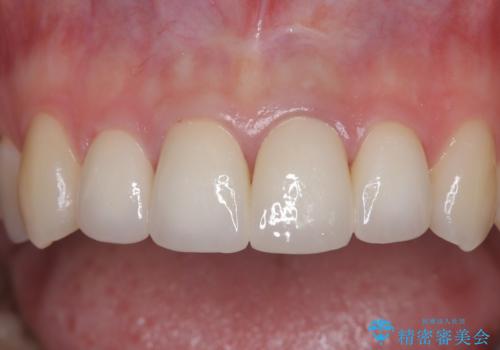

【オールセラミッククラウン】前歯の見た目が気になる!

根管の充填物も不十分だったため根管治療からやり直しオールセラミッククラウンで治療を行いました。

根管の中が空洞のままで被せ物と歯のきわも合っておらず適合が悪い状態でした。根尖部付近にはパーフォレーションリペア修復の痕がありました。バイオシーシーラーを使用しシングルポイント法で充填しました。空洞があると細菌が増える環境になってしまうので、根管治療からやり直し、緊密に充填しました。被せ物の見た目も大変満足していただけました。